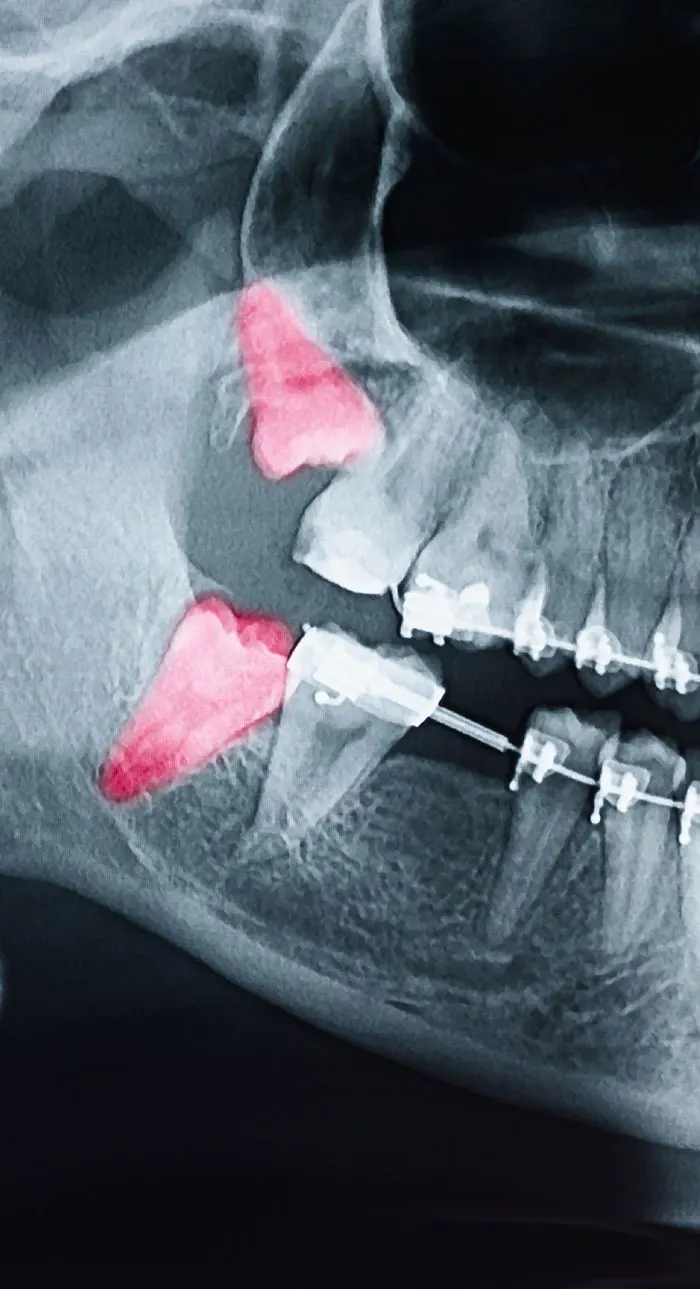

Wisdom teeth are often extracted if they’re impacted, causing pain, or crowding surrounding teeth. Your dentist will always explore all options before recommending removal, but sometimes extraction is the best way to protect your long-term oral health.